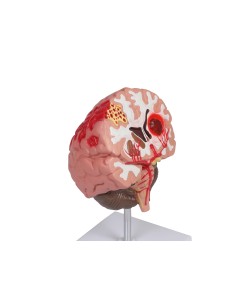

3B Modèle anatomique scientifique de l'œil pathologique, agrandissement 5 fois F17